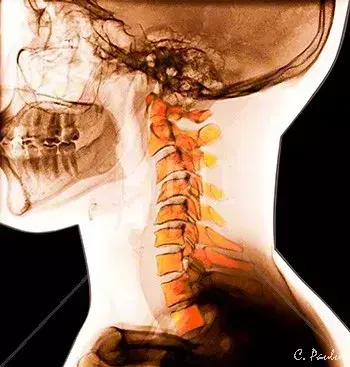

图2、正常的颈椎侧位片

图 6、颈椎生理曲度变直

图7、颈椎侧位片,生理曲度返弓。